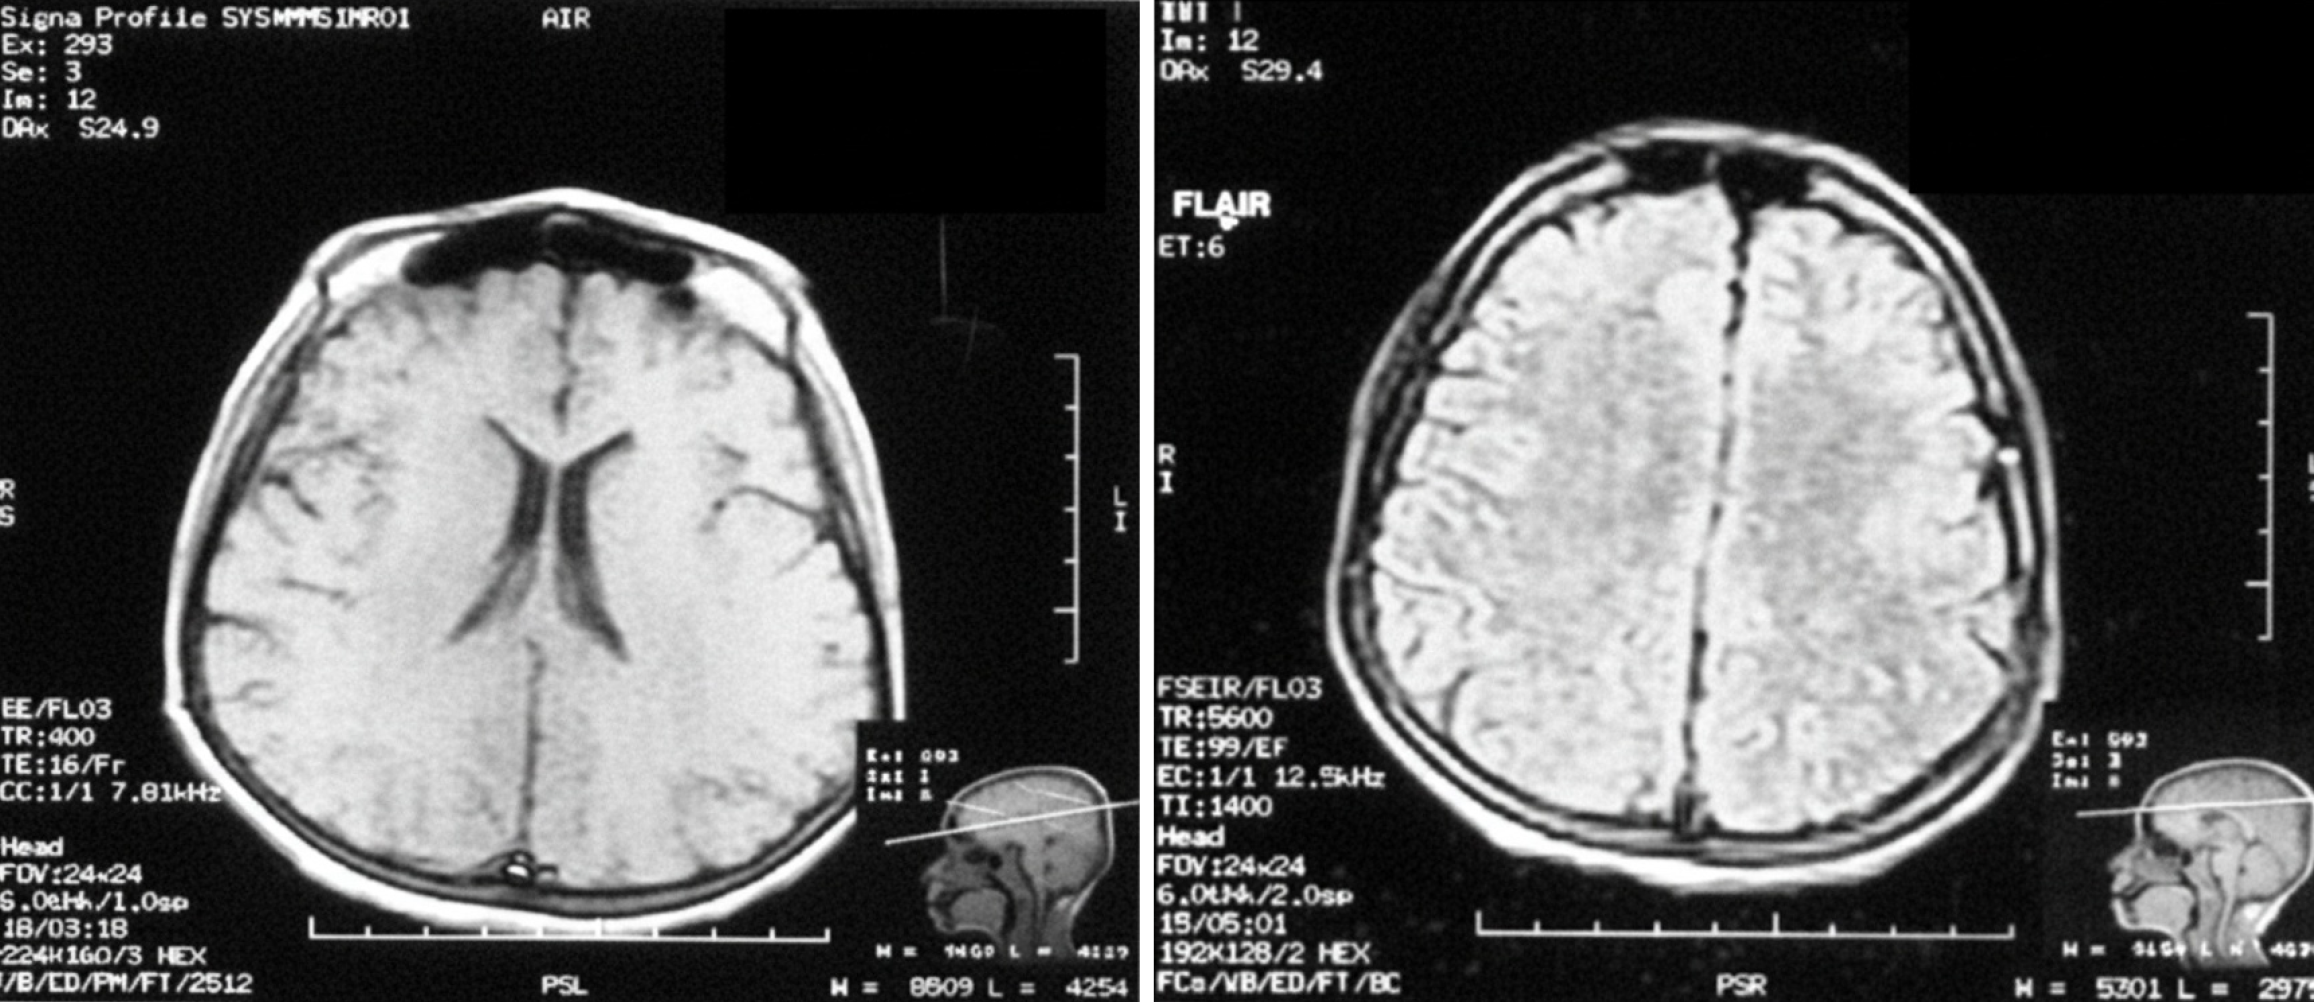

Figure 3

The shows normal findings of the magnetic resonance imaging of the brain.